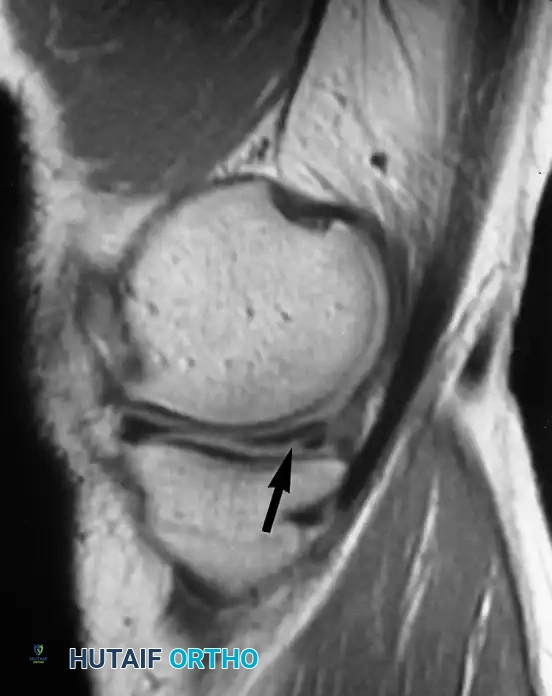

تقييم الغضاريف الهلالية

تتسبب الحالات المرضية للغضروف الهلالي في نسبة كبيرة من آلام الركبة والإعاقة الحركية. تظهر الغضاريف الهلالية الطبيعية في الرنين المغناطيسي كأشكال مثلثة داكنة اللون. عندما يحدث تغير في هذا اللون الداكن وتظهر إشارات مضيئة داخله، يصنف أطباء الأشعة هذه التغيرات إلى ثلاث درجات:

- الدرجة الأولى: مناطق دائرية من الإشارة المتزايدة داخل الغضروف.

- الدرجة الثانية: مناطق خطية من الإشارة المتزايدة لا تصل إلى السطح.

- الدرجة الثالثة: خط غير طبيعي يمتد ليصل إلى السطح المفصلي العلوي أو السفلي.

من المهم جدا للمرضى أن يعرفوا أن الدرجة الأولى والثانية لا تمثل تمزقا حقيقيا، بل هي مجرد تغيرات تنكسية طبيعية لا تحتاج لتدخل جراحي. فقط الدرجة الثالثة هي التي تعبر عن تمزق حقيقي في الغضروف.

يجب تحديد التمزق بدقة من حيث موقعه وشكله سواء كان أفقيا، عموديا، معقدا، أو شعاعيا.